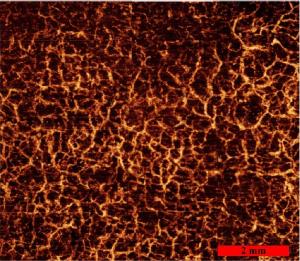

Correlation Mapping Optical Coherence Tomography (cmOCT)

The TOMI group has an interest in using Optical Coherence Tomography (OCT) system for Structural and Microcirculation Imaging. To facilitate microcirculation imaging using OCT, we have developed an algorithm called Correlation Mapping Optical Coherence Tomography. The technique is achieved as a processing step on OCT intensity images and does not require any modification to OCT hardware. We use this method for a wide range of applications from dermatology to intracoronary applications. The algorithm has been implemented in Java and we have made the code open source. It is hosted on GitHub here, feedback and input are always welcome!